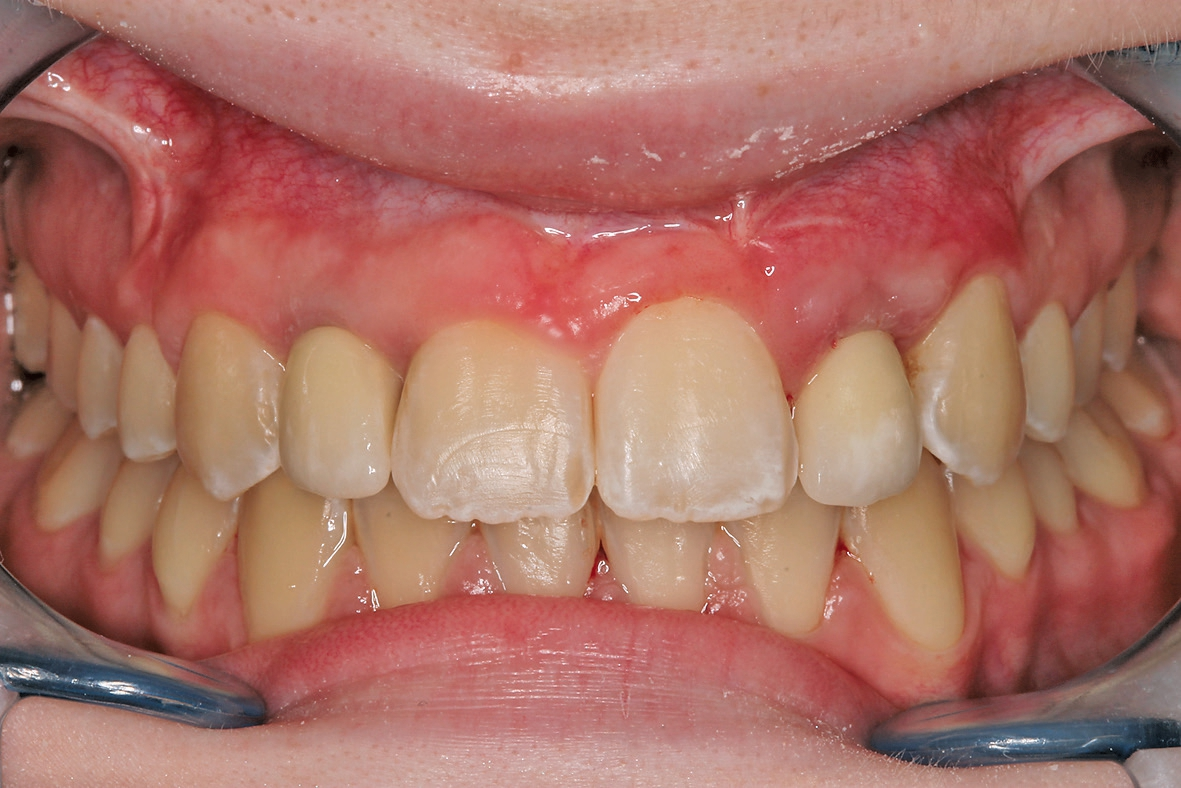

Nach weiterer mehrmonatiger Weichgewebsausformung durch die beiden Langzeitprovisorien 12 und 22 wurden dann reine Zirkoniumkronen zunächst provisorisch eingesetzt und die Patientin in die hauszahnärztliche Versorgung zurücküberwiesen (Abb. 16).

Grundsätzlich ist die Implantatversorgung bei Kindern, Jugendlichen oder jungen Erwachsenen ein sehr komplexes zahnärztliches Gebiet, weil laut einer Studie von Terheyden et. al es bei Adoleszenten (12-18 Jahre) eine durchschnittliche Infraokklusion von 3 mm (max. 8 mm) resultieren kann und die Implantatprognose sich auf zirka 93% beläuft (gegenüber durchschnittlichen Implantaterfolgsquoten von 98-99%). Insofern fordert Terheyden et. al, dass bei „Adoleszenten, die bis jetzt tradierte harte Grenze des 18. Lebensjahres eher einer differenzierten Betrachtung weichen und ersetzt werden sollte durch das Abwarten des pubertären Wachstumsspurts“. Des Weiteren fordert Terheyden et. al, dass eine möglich auftretende Infraokklusion therapeutisch antizipiert und die etwas reduzierte Implantatprognose den Patienten und Eltern mitgeteilt werden sollte. Die Kommunikation mit der Patientin respektive der Eltern der Patientin kommt eine ganz entscheidende Bedeutung zu, insbesondere da möglicherweise erneute Zirkoniumkronen bei vorausgesetzt richtiger Implantatpositionierung im Laufe der Phase des jungen Erwachsenen (18-31 Jahre) angefertigt werden müssen zum Ausgleich einer sich entwickelnden Infraokklusion. Auf der anderen Seite ist bei zu langem Warten des chirurgischen Behandlungsbeginns die Gefahr, dass die sowieso bestehende laterale/vertikale Atrophie soweit voranschreitet, dass eine Nutrition des aufzulagernden Blockes (autolog/allogen) aufgrund fehlender Spongiosa nicht mehr gegeben ist. Gerade bei hochgradiger Atrophie ist der eingeschmolzene Spongiosa-Anteil sowohl im Oberkiefer als auch im Unterkiefer aufgrund der Schrumpfung in der Horizontalen so ausgedünnt, dass letztendlich nur noch eine bukkal-palatinale oder bukkal-linguale Kompakta als Empfängergebiet für das Transplantat zur Verfügung steht mit entsprechender Mangelversorgung des Transplantates. Die Spongiosa ist von entscheidender Bedeutung, damit die Transplantate (autologe/allogene) entsprechend einheilen und durch eigene Knochenzellen ersetzt werden können. Nach Festlegung des richtigen Implantationszeitpunktes respektive Zeitpunkt der präoperativen Augmentation sollte berücksichtigt werden, dass die skelettale Entwicklung junger Mädchen zwei Jahre dem skelettalen Wachstum von Jungen voraus ist. Nach Björg und Helm 1967 tritt der erste Wachstumsspurt bei Jungen gemäß mit 13 Jahren und bei Mädchen mit 11 Jahren auf. Bezüglich des Augmentationsprotokolls und der verwendeten Techniken findet in den letzten Jahren ein Paradigmenwechsel von Seiten des autologen Knochentransfers (Goldstandard) zu minimalinvasiveren Alternativtechniken (allogene Schalentechnik nach Esser et. al., techniksensitiv) respektive bei guter Auflagemöglichkeit mit Hilfe von CAD/CAM erstellten kortikospongiösen Blocktransplantaten. Der Autor arbeitet seit 2005 mit den humanen allogenen Knochenblockimplantaten, die mittlerweile von mehreren Firmen (Argon, Osteograft, DIZG, Zimmer, Tutoplast, Botiss, Straumann, etc.) nach verschiedenen Herstellermethoden Tutoplast-prozessiert, ?-Sterilisierung, Peressigsäure etc. hergestellt werden und seitens des Autors bis dato 702 Mal verwendet wurden. Dabei wurden bei der Erfolgsrate Werte von 95,42% im Oberkiefer und 89,19% im Unterkiefer erzielt, was einer Gesamterfolgsquote von 93,45% entspricht.